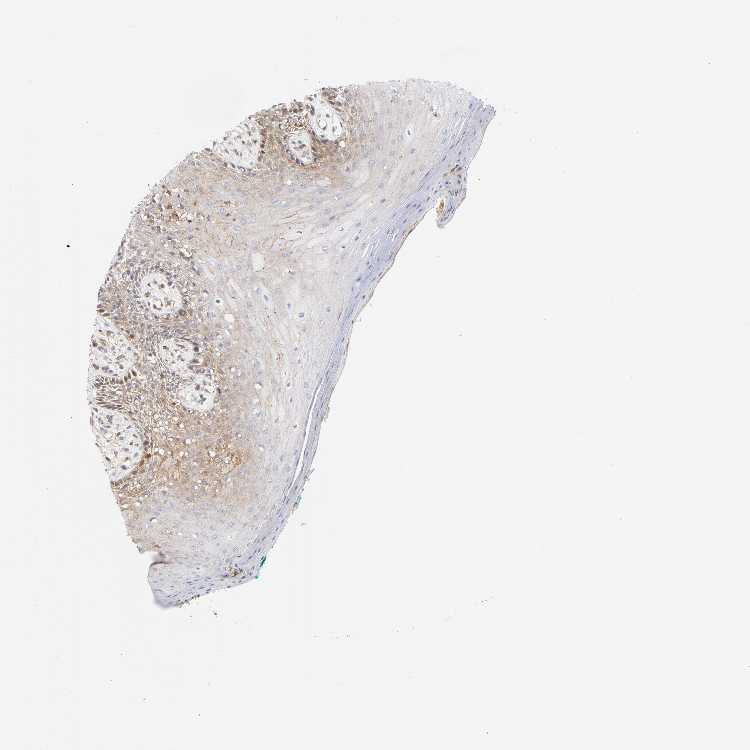

TISSUE PRIMARY DATA ORAL MUCOSA Show tissue menu

ORAL MUCOSA - Antibody stainingi

Antibody staining in the annotated cell types in the current human tissue is reported as not detected, low, medium, or high, based on conventional immunohistochemistry profiling in selected tissues. This score is based on the combination of the staining intensity and fraction of stained cells.

Each image is clickable and will lead to virtual microscopy that enables deeper exploration of all samples and also displays staining intensity scores, fraction scores and subcellular localization as well as patient and tissue information for each sample.

Antibody CAB004312

Squamous epithelial cells Medium